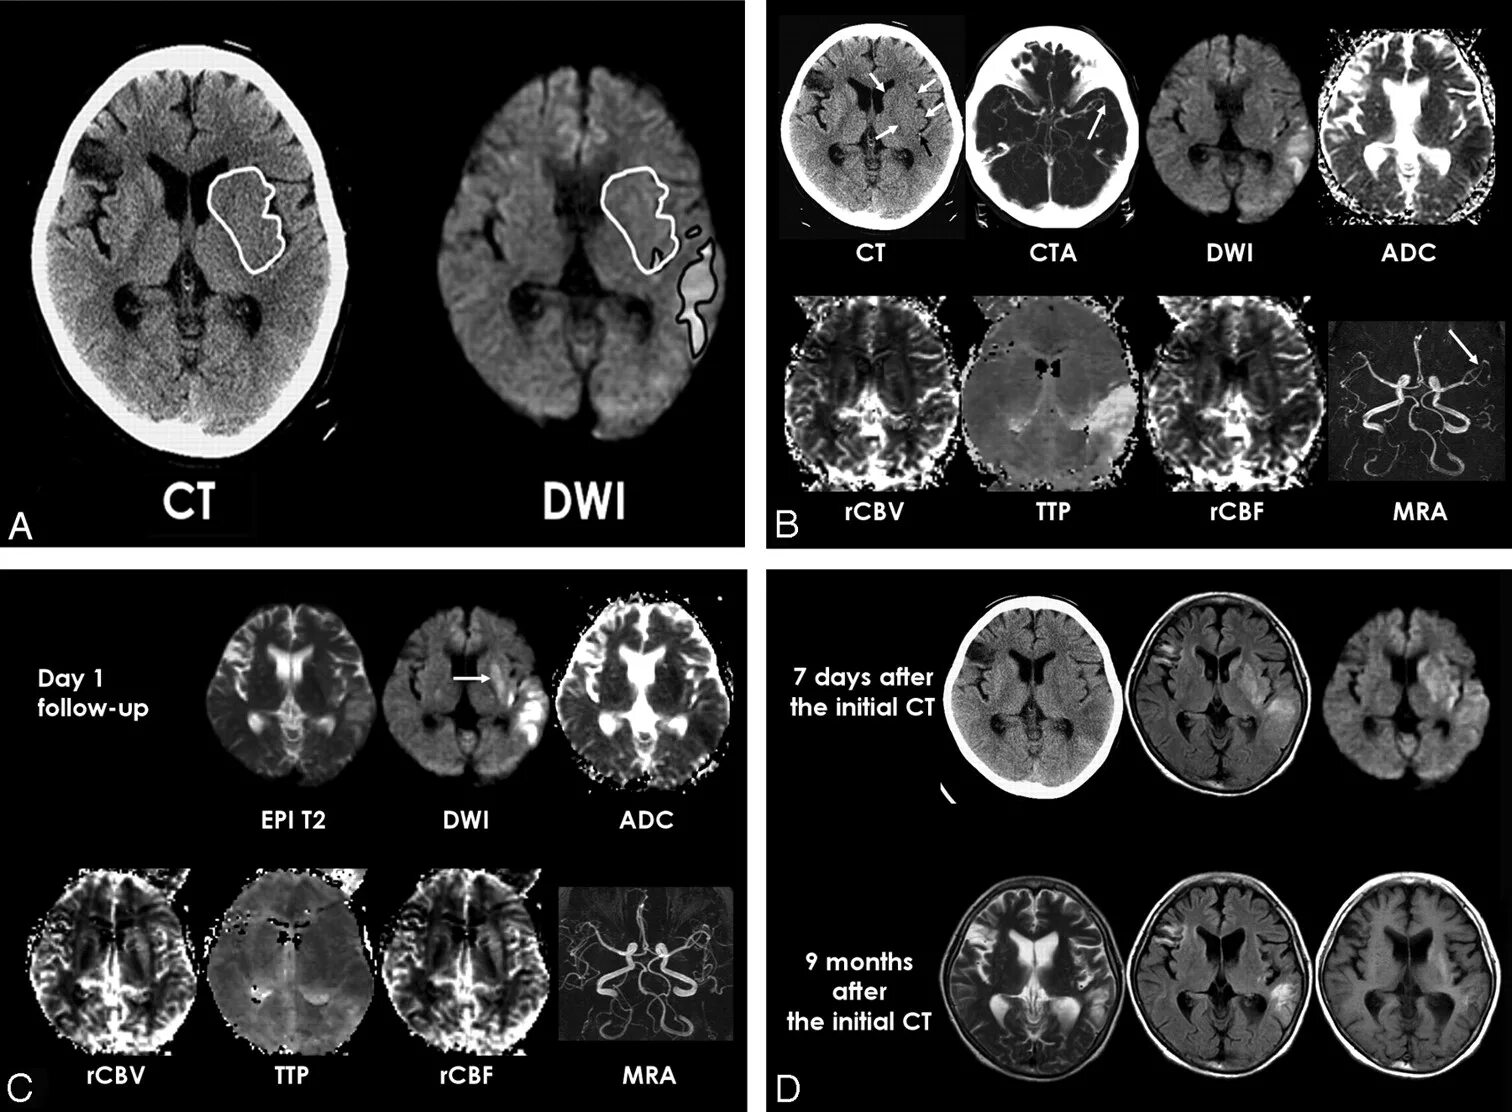

Мрт височных костей в режиме dwi